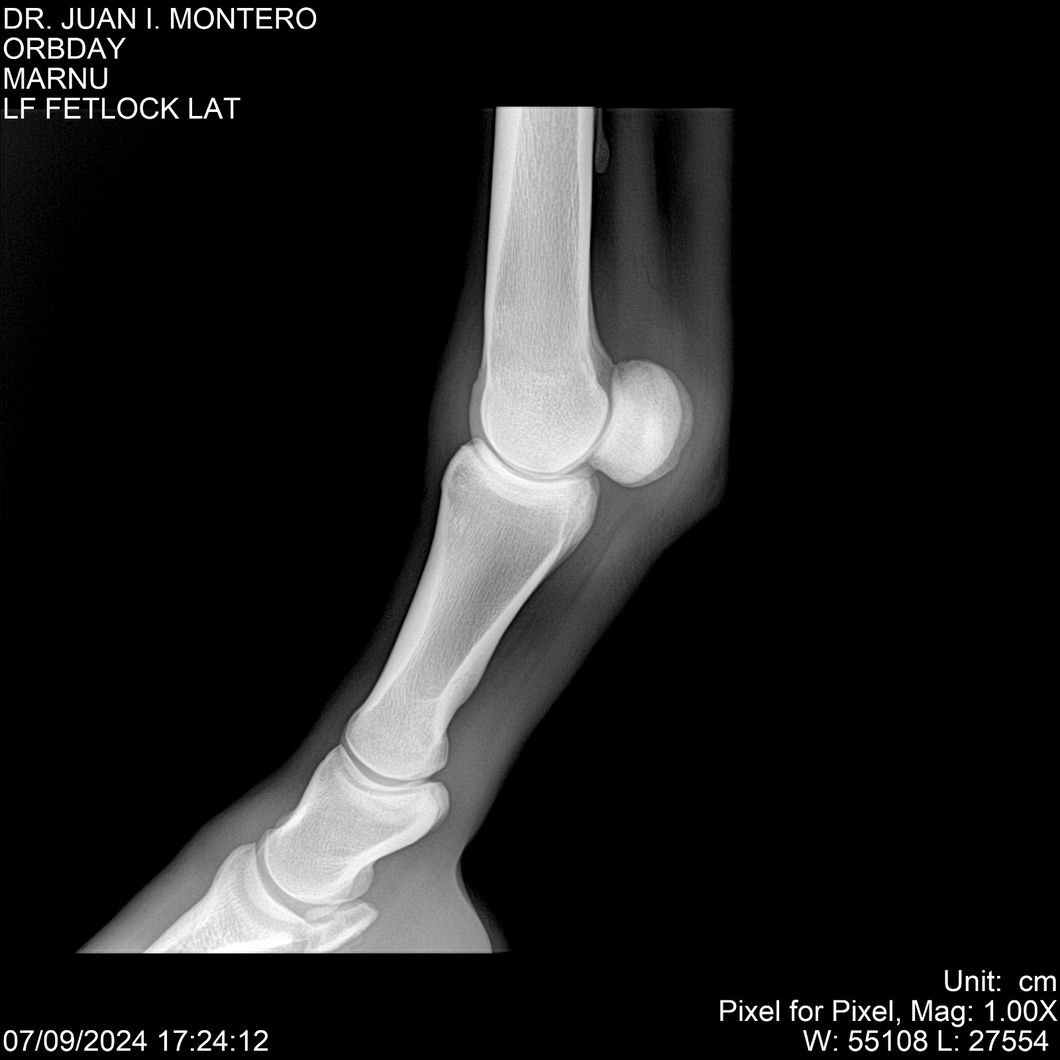

• Empresa: Abelenda N. R., Walter Hugo